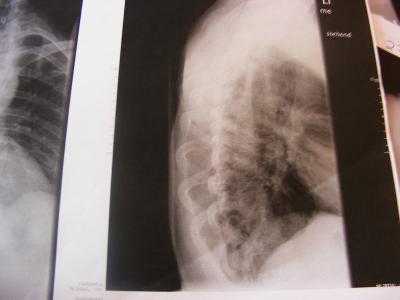

Nun habe ich konkrete neue und hoffentlich dann auch richtige Zahlen (ich kann auch nur die Zahlen angeben - welche ich von den jeweiligen "Orthopäden" bekomme) vom Grad der Krümmungen - ich hatte zu dem Zeitpunkt als ich mich angemeldet habe einen anderen Arzt mit dem ich nicht zufrieden war (was ich ja hier häufiger gelesen habe) und habe gewechselt, von dem Orthopäden hatte ich die Angaben in meiner Anmeldung, dann kam Orthopäde Nr.2 welcher mich gern auf der Schlachtbank gesehen hätte - heute nun Orthopäde Nr. 3 und bekam diese Angaben: Krümmung oben 63° Krümmung unten 56° dazu eine schwere Arthrose in der linken Schulter welche dort die starken Schmerzen verursacht! Ein Korrekturkorsett ist nicht mehr machbar, soll mit KG nach Schroth anfangen für die Krümmung BWS, jetzt habe ich erst einmal KG für die Arthrose in der Schulter bekommen, in der LWS hat sich die WS von selbst angefangen zu versteifen, daher auch die Aussage das ich kein Korsett mehr bekommen kann! Ich werd die Bilder mal abfotografieren und dann kann sich jeder mal selbst ein Bild davon machen!

So hier noch zwei Bilder....

Ich würde dir dennoch die Meinung eines Skoliose-Spezialisten empfehlen, der erstens die Korsettfrage klären kann und zweitens auch mal ordentliche Bilder von der Wirbelsäule macht, deine Bilder sind leider Teilaufnahmen.